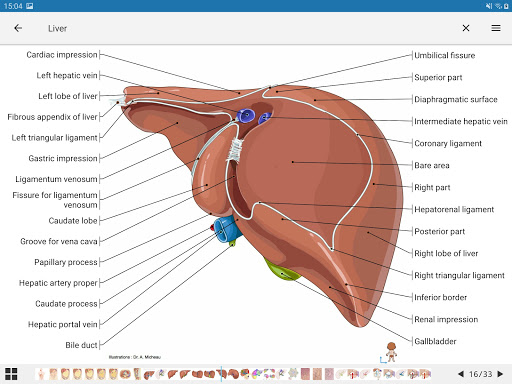

IMAIOS e-Anatomy adalah atlas anatomi manusia untuk dokter, ahli radiologi, mahasiswa kedokteran, dan teknisi radiologi. Dapatkan cuplikan lebih dari 26.000 gambar medis dan anatomi secara gratis sebelum berlangganan atlas anatomi manusia terperinci kami.

e-Anatomy memiliki lebih dari 26.000 gambar yang berisi serangkaian gambar dalam tampilan aksial, koronal, dan sagital serta radiografi, angiografi, gambar diseksi, bagan anatomi, dan ilustrasi. Semua gambar medis diberi label dengan cermat, lebih dari 967.000 label tersedia dalam 12 bahasa termasuk Terminologia Anatomica Latin.

- Ketuk label untuk menampilkan struktur anatomi